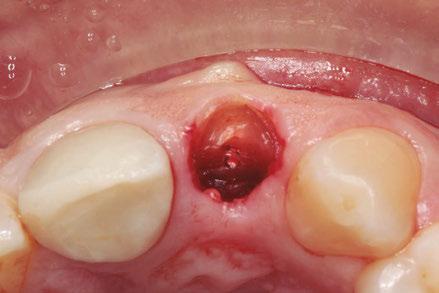

–Implante inmediato en incisivo lateral superior con técnica de «Socket Shield» y acceso vestibular para legrado de la lesión periapical, por el Dr. Ignacio Tormo Jiménez y cols. [106]